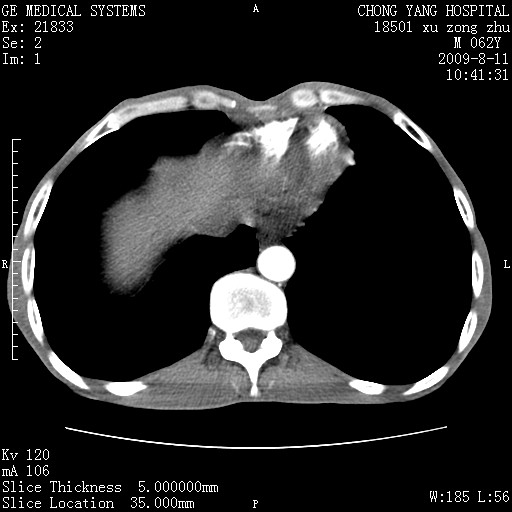

以下是引用杀毒软件在2009-8-11 16:35:00的发言:[br]肝内胆管扩张局限于左叶,胆管内有结石伴肝外胆管结石,胆管壁增厚呈弥漫性并发腹腔积液,胰腺边界模糊。[br][br]考虑---胆总管及肝内胆管结石继发胆管炎及胰腺炎,左肾下极囊肿,腹水。

以下是引用zjzjr在2009-8-11 17:35:00的发言:[br]肝内胆管扩张局限于左叶,胆管内有结石伴肝外胆管结石,胆管壁增厚呈弥漫性并发腹腔积液。[br][br]考虑---胆总管及肝内胆管结石继发胆管炎,左肾下极囊肿,腹水。